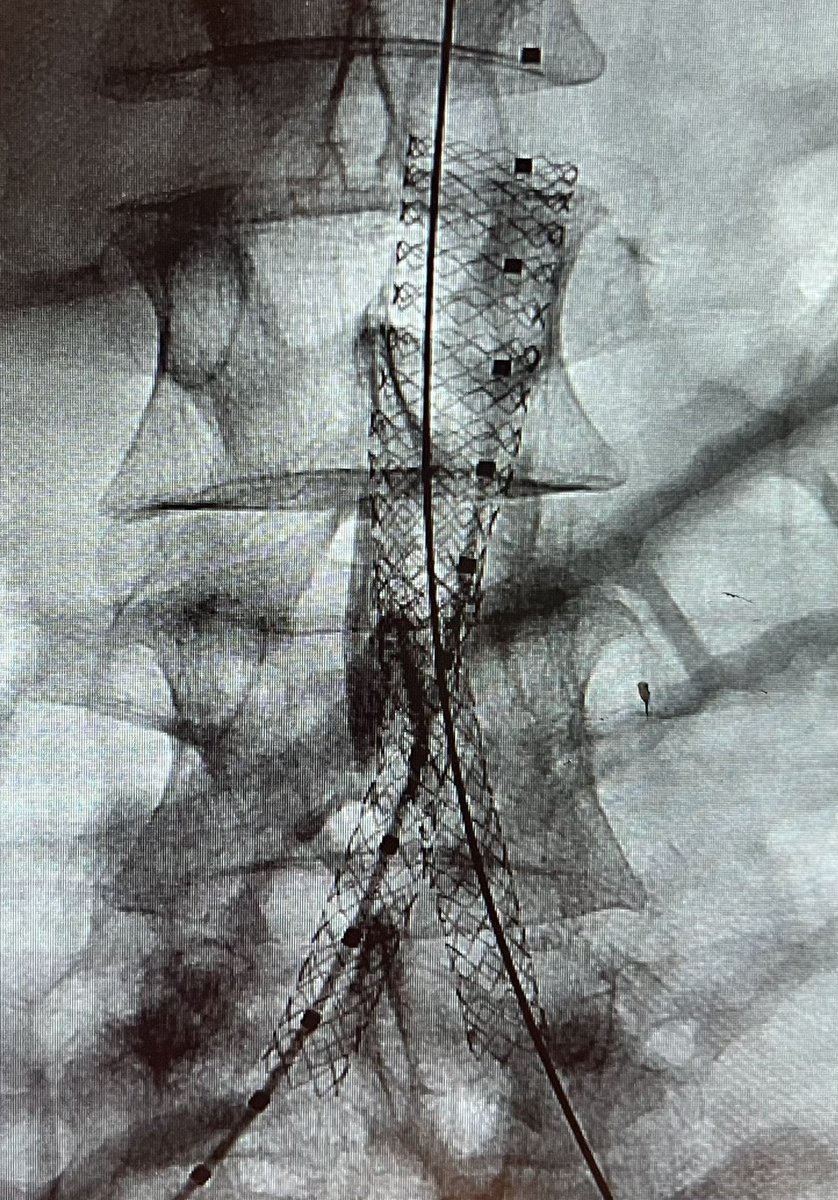

Aortoiliac occlusive disease with significant claudication s/p CERAB technique with 11mm VBX at aorta (post dilated to 16mm proximally and 14 distally) and 8mm kissing VBX with our very own @GZlotchenko @pj_rochon @LWalkerMD @CURadiology @SIRspecialists @SIR_ECS

6

17

89